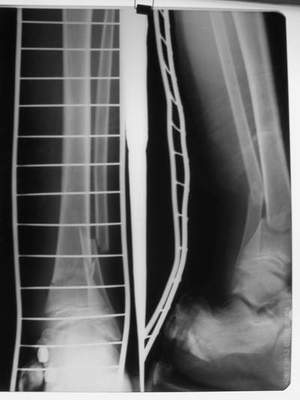

A> Это сросшийся перелом малоберцовой кости. И ложный сустав

A> н\3 б\берцовой кости.

Нашел в комп-ре схожий случай:

1) з/репозиция, 2) фиксация 2 спицами, 3) аппарат, 4) фиксационные

спицы удалены...

А можно было наложить аппарат и по поводу ложного сустава...

По крайней мере не было бы укорочения (пусть и в 2 см)...